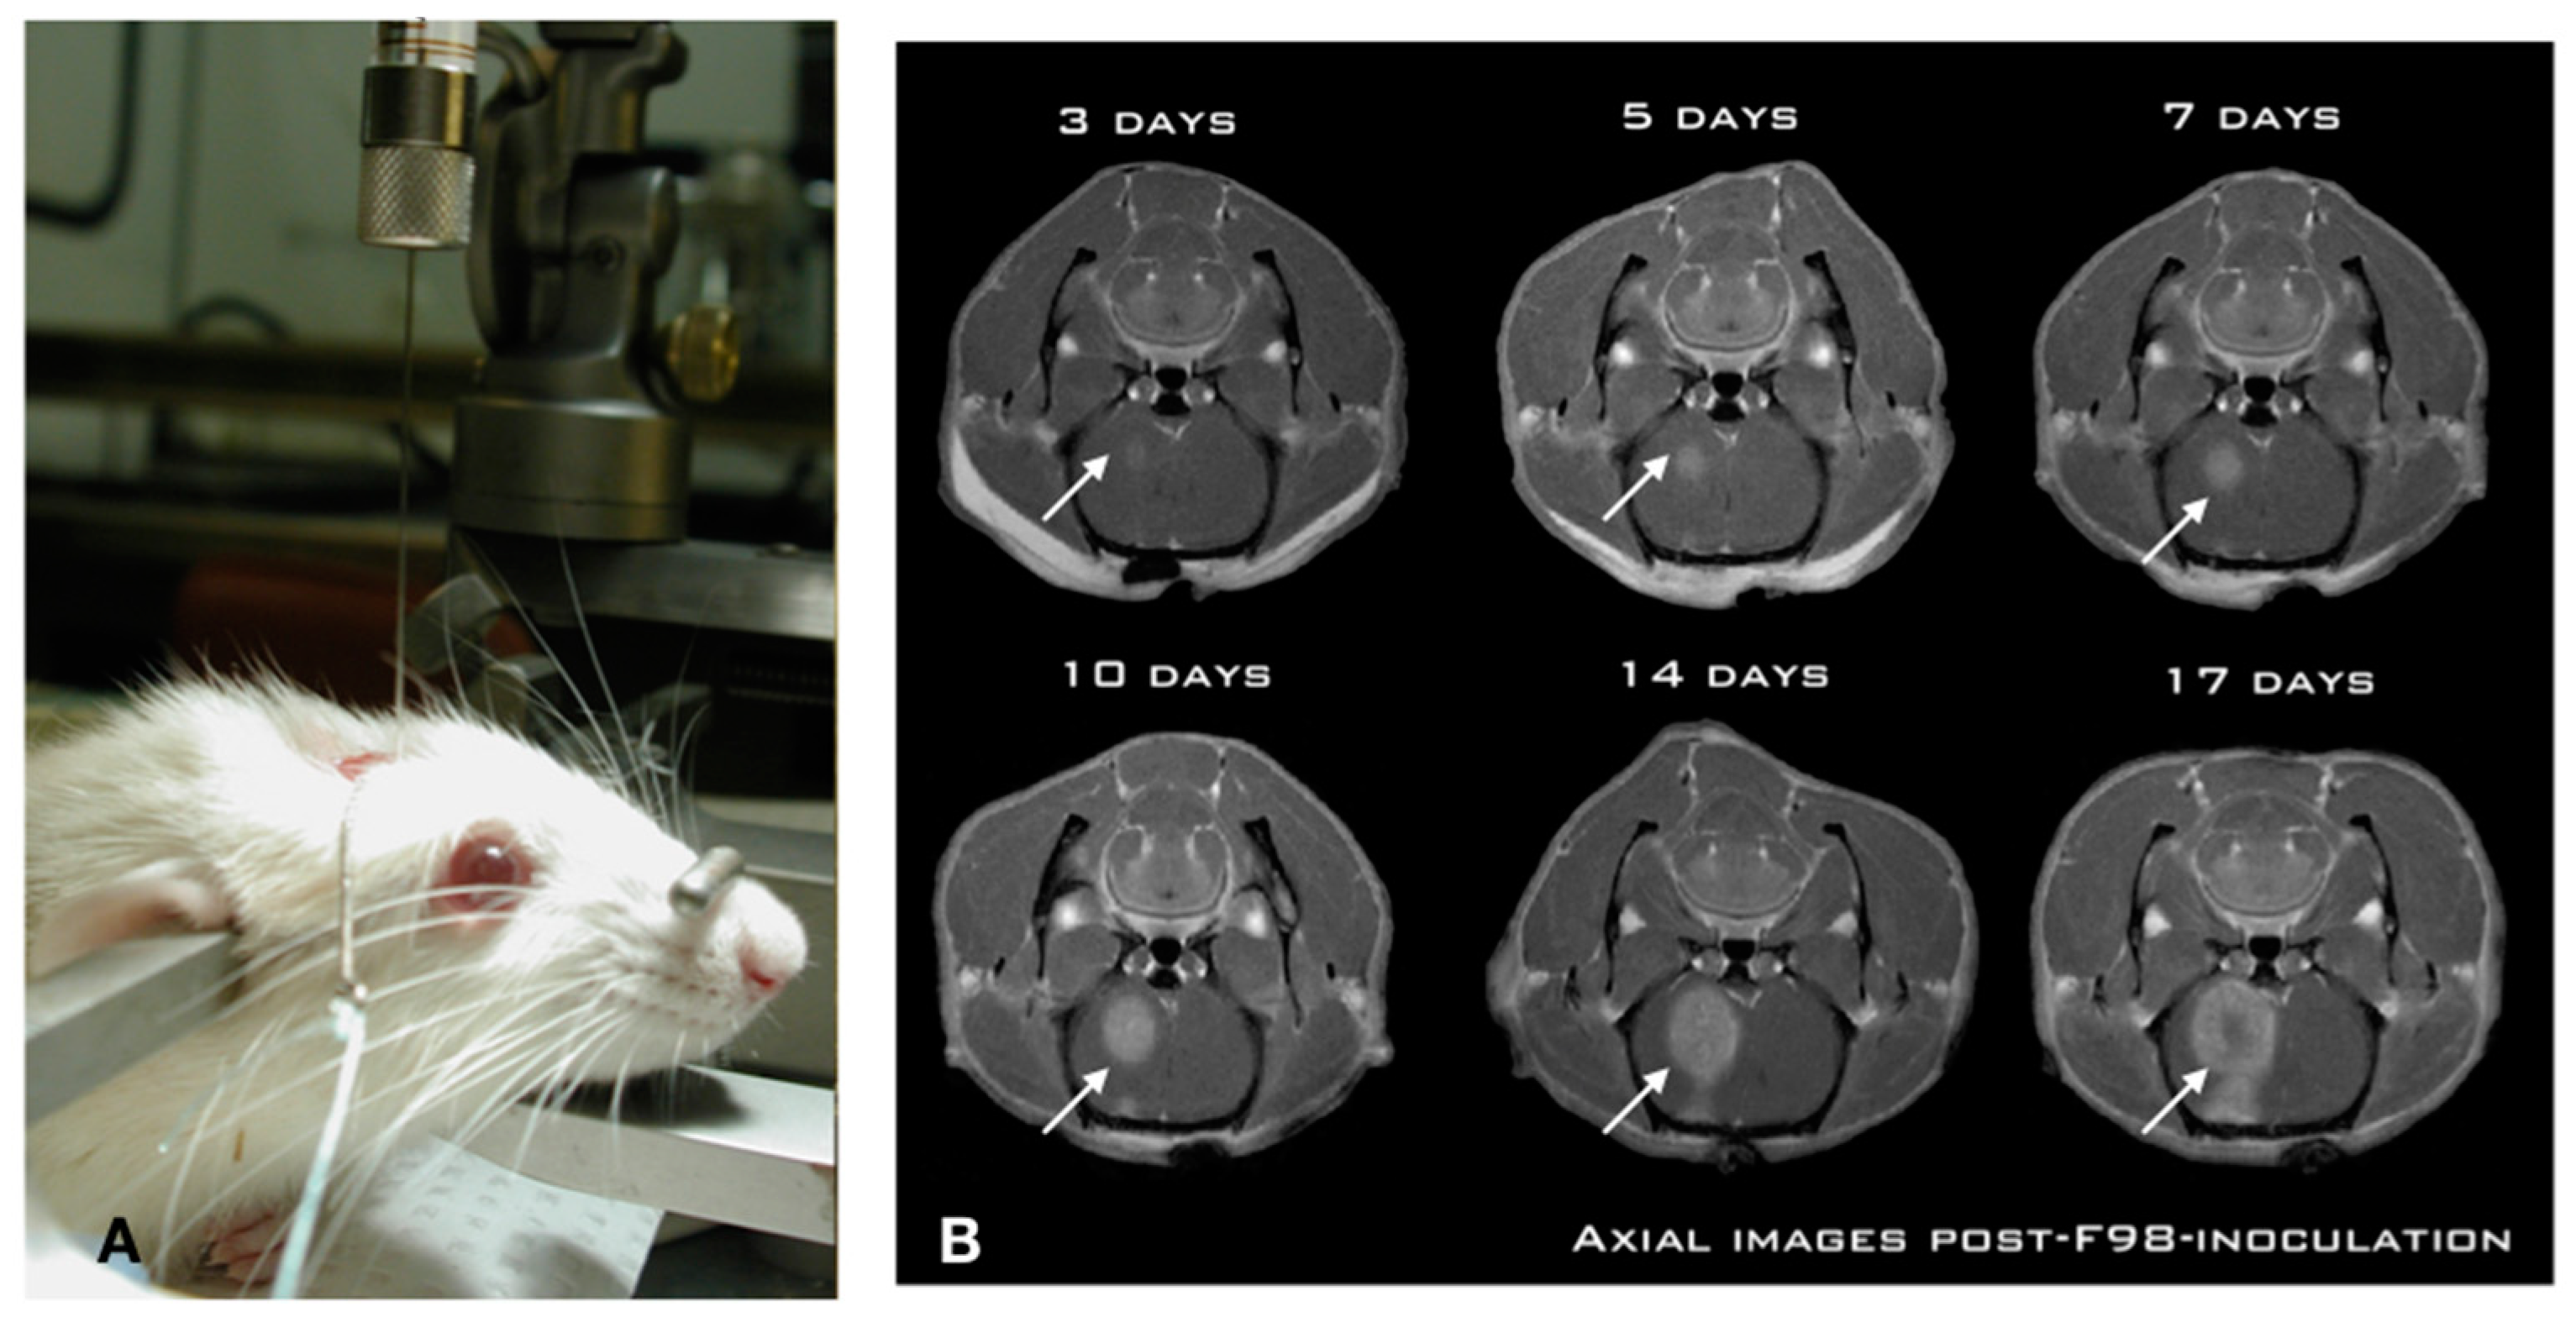

While numerous investigators have studied CIAC and BBBD over the years, we undertook a thorough pre-clinical characterization in the Fischer-F98 model to ascertain, objectivate, and measure the delivery advantage provided by both approaches. We first characterized the F98-Fischer glioma model as a benchmark for our delivery studies. The model was found to be highly predictive and reproducible in term of tumor growth dynamics and animal survival (Figure 1).

Using a standardized implantation procedure, the tumor-take has systematically been 100%, with a median survival of 26 ± 2 days [25,26]. Figure 1A shows the position of the animal in the stereotactic frame for precise insertion of the needle in the brain of the animal using a precise and standardized coordinate system [25]. This is paramount for reproducibility across experiments. Indeed, a free-hand implantation technique which is frequently employed in the literature is inadequate for these types of studies. Likewise, we found that the use of a micro-infusion pump is essential in minimizing tissue damage and associated inflammatory reaction triggered by the implantation process [25]. The slow (1 μL/min) and steady infusion rate and the low volume (10,000 cells in 5 μL) ensures minimized cerebral tissue disruption and prevents the backflow along the implantation track commonly associated with these models [25,26]. This produces a constant pattern of tumor growth in the right hemisphere of the animal, where the tumor is already noticeable at day 3 post-implantation (Figure 1B), and starts to produce an alteration in consciousness around day 26. Experimental treatments are performed at day 10 post-implantation, when the tumor has reached a significant size (Figure 1B), without altering the neurological functions of the animal [27,28,29,30].

Figure 1. The Fischer-F98 glioma model shows a reproducible and predictable growth pattern. (A) The infusion of the cell suspension is accomplished using a slow steady perfusion with a micro-infusion pump. Also, 10,000 cells are infused at a rate of 1 μL/min over 5 min. (B) Coronal views of an implanted animal at days 3, 5, 7, 10, 14 and 17 post-implantation. Notice the gradual progression of the gadolinium enhancement on the MR scans in the right hemisphere (arrows) depicting the steady tumor progression. The animal starts to develop faint subtle symptoms (lateralization) at day 14, that culminate at day 26 ± 2 days.